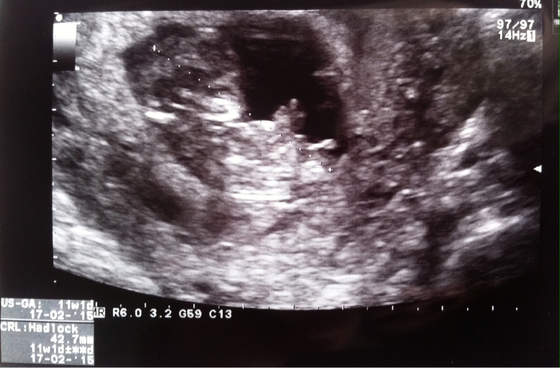

Forumowe ciocie przedstawiam najnowsze zdjęcie naszego obcego , juz bardziej wyglada jak człowiek ale podczas USG jeszcze troszke kosmita

Jak dobrze się przyjrzyjcie to zobaczycie co za mała świnka pokazuje nam !!! Niestety środkowy palec

całe USG mamy nagrane na płytkę wiec jest co oglądać , machal raczkami, drapal sie po głowie a na samym początku przedstawił sie środkowym palcem

Sprawdzał przeciętność karkową obcego, wyszła jak na ten moment 2,0 , niestety musiał nim wstrząsnąć bo nie chciał współpracować , uparte to nasze dziecko